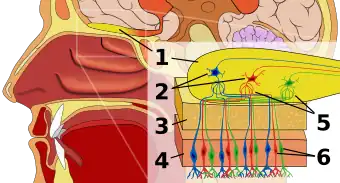

1: Olfactory bulb 2: Mitral cells 3: Cribriform plate 4: Olfactory epithelium 5: Glomerulus 6: Olfactory receptor neurons | |